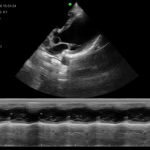

| Modo de escaneo | B, B/M, Color, PW |

Modos de escaneo: B, B/M, Color, PW

Velocidad de imagen: 24 fps